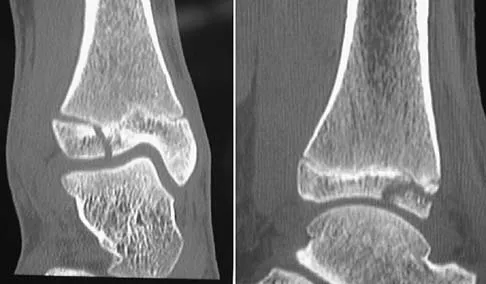

A 21-year-old professional baseball player has had painful catching and stiffness in his dominant right elbow for the past year. Examination reveals a flexion contracture of 2 degrees and mild pain with full elbow flexion. Radiographs are shown in Figures 33a and 33b. The most effective management should consist of

Explanation